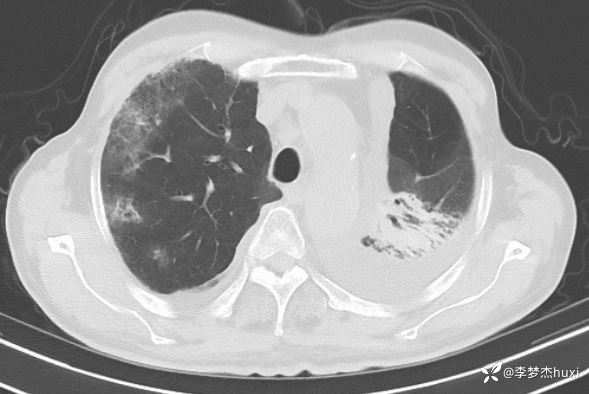

简要病史:患者于 1 年余因咳嗽查胸部增强 CT:考虑左肺上叶恶性肿瘤样病变,双肺多发结节。行肺穿刺活检,病理:鳞状细胞癌,诊断:左肺鳞癌(cT3N0M0 IIB 期)局部晚期。2022-03-1 7、2022-04-07、2022-04-30、2022-06-24 、2022-07-17、2022-08-12 给予白蛋白结合紫杉醇 +卡铂+替雷利珠单抗化疗 6 周期;2022-09-03、2022.10.05 给予替雷利珠单抗免疫治 2 周期。 2022-11-29 开始给予肺部肿瘤放疗治疗,放疗结束后患者无明显不良反应出院。2023-04-0 1、2023-05-01 给予替雷利珠单抗免疫治疗 2 周期。患者于入院前 3 天出现咳嗽、咳痰,为白粘痰,活动后喘息,伴胸闷、憋气,

临床诊断:肺炎,肺癌

讨论:入院后新冠肺炎,加抗病毒治疗,及莫西沙星后哌拉西林他唑巴坦,呼吸道症状好转,血小板下降,20~30,促血小板生成素、激素等效果不明显。